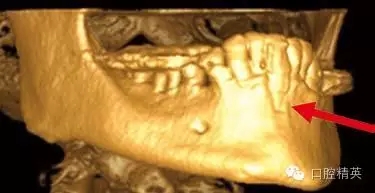

圖3a:術(shù)后的三維影像重建給外科醫(yī)生對(duì)手術(shù)入路的回顧以提示。對(duì)于這一病例進(jìn)行了Caldwell-Luc術(shù)式,用球鉆在上頜竇側(cè)壁做一窗口,直接入路取出種植體。

圖3b:醫(yī)生再來臨床觀察到的情況并不能準(zhǔn)確的反應(yīng)粘膜下牙槽骨的真實(shí)形態(tài)

圖3c:術(shù)前用ICAT椎體束CT成像診斷,斷層片顯示6,7號(hào)牙頰側(cè)牙槽骨根方凹陷,需要再種植體術(shù)中或術(shù)前植骨

另外一個(gè)棘手的問題和上頜骨前部的解剖結(jié)構(gòu)有關(guān)。(圖3)這種病例,從臨床檢查上看,上頜骨量非常豐富,頜骨矢狀斷面呈三角形,符合Scott Ganz醫(yī)生所描述的“三角形骨”理論。這一理論幫助確定牙槽骨固有形態(tài),判斷最佳的種植體植入位置。

如這個(gè)病例展示的,CBCT斷層掃描揭示了牙槽骨根方的凹陷。這樣就避免了術(shù)中的意外,醫(yī)生可以在術(shù)前完善的計(jì)劃,向患者交代清楚手術(shù)方法、風(fēng)險(xiǎn)、以及植骨所需增加的相應(yīng)費(fèi)用等問題。在兩維的放射影像中是無法預(yù)先觀察到這個(gè)問題的。僅使用兩維放射診斷帶來的另一個(gè)并發(fā)癥是種植體折斷。(圖4)前面提過,兩維曲面斷層影像難以獲得精確定位,有的醫(yī)生為了避免損傷下頜神經(jīng)管而應(yīng)用短種植體。這樣做的結(jié)果是增加了修復(fù)體-種植體長(zhǎng)度比,隨著時(shí)間的流逝會(huì)造成骨吸收,最終可能導(dǎo)致種植體折斷。